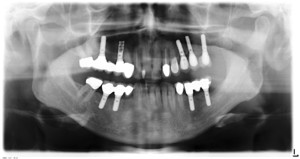

Zahnimplantate sind eine sehr elegante und zeitgemässe Lösung, um fehlende Zähne zu ersetzen. Von der Einzelzahnlücke bis zum zahnlosen Kiefer sind Implantate einsetzbar.